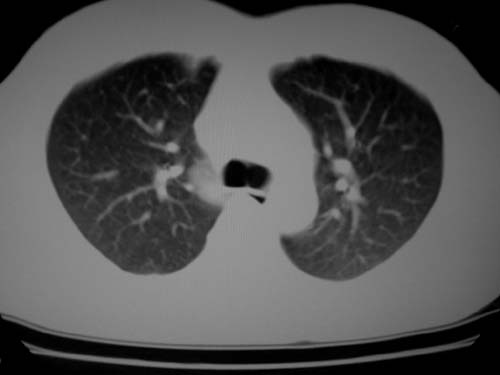

标题: CT19540: 31岁。自述结核性胸水治疗两个月后,在外院拍x线发 [打印本页]

标题: CT19540: 31岁。自述结核性胸水治疗两个月后,在外院拍x线发

右侧胸壁结节状软组织影伴相应肺叶内受侵,伴右侧胸腔积液。考虑:结核性可能大。

病灶也是发生于结核球好发部位,支持结核

右侧胸壁结节状软组织影伴相应肺叶内受侵,伴右侧胸腔积液,结合临床,首先考虑结核。

1)考虑右侧结核性胸膜结节。2)右侧胸膜增厚+包裹性胸腔积液。

结核性脓胸、肺内结核?